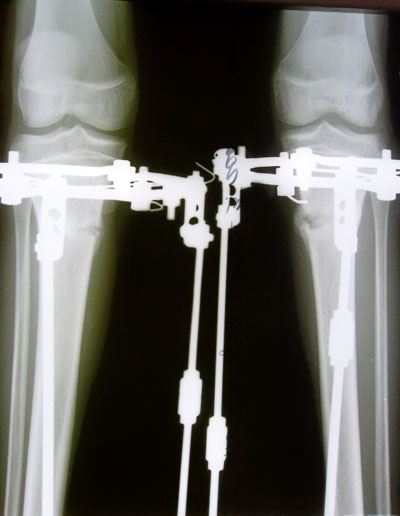

Дата операции 27.05.2014г.

Дата снятия аппаратов 22.07.2014г.

Срок лечения 55 дней.